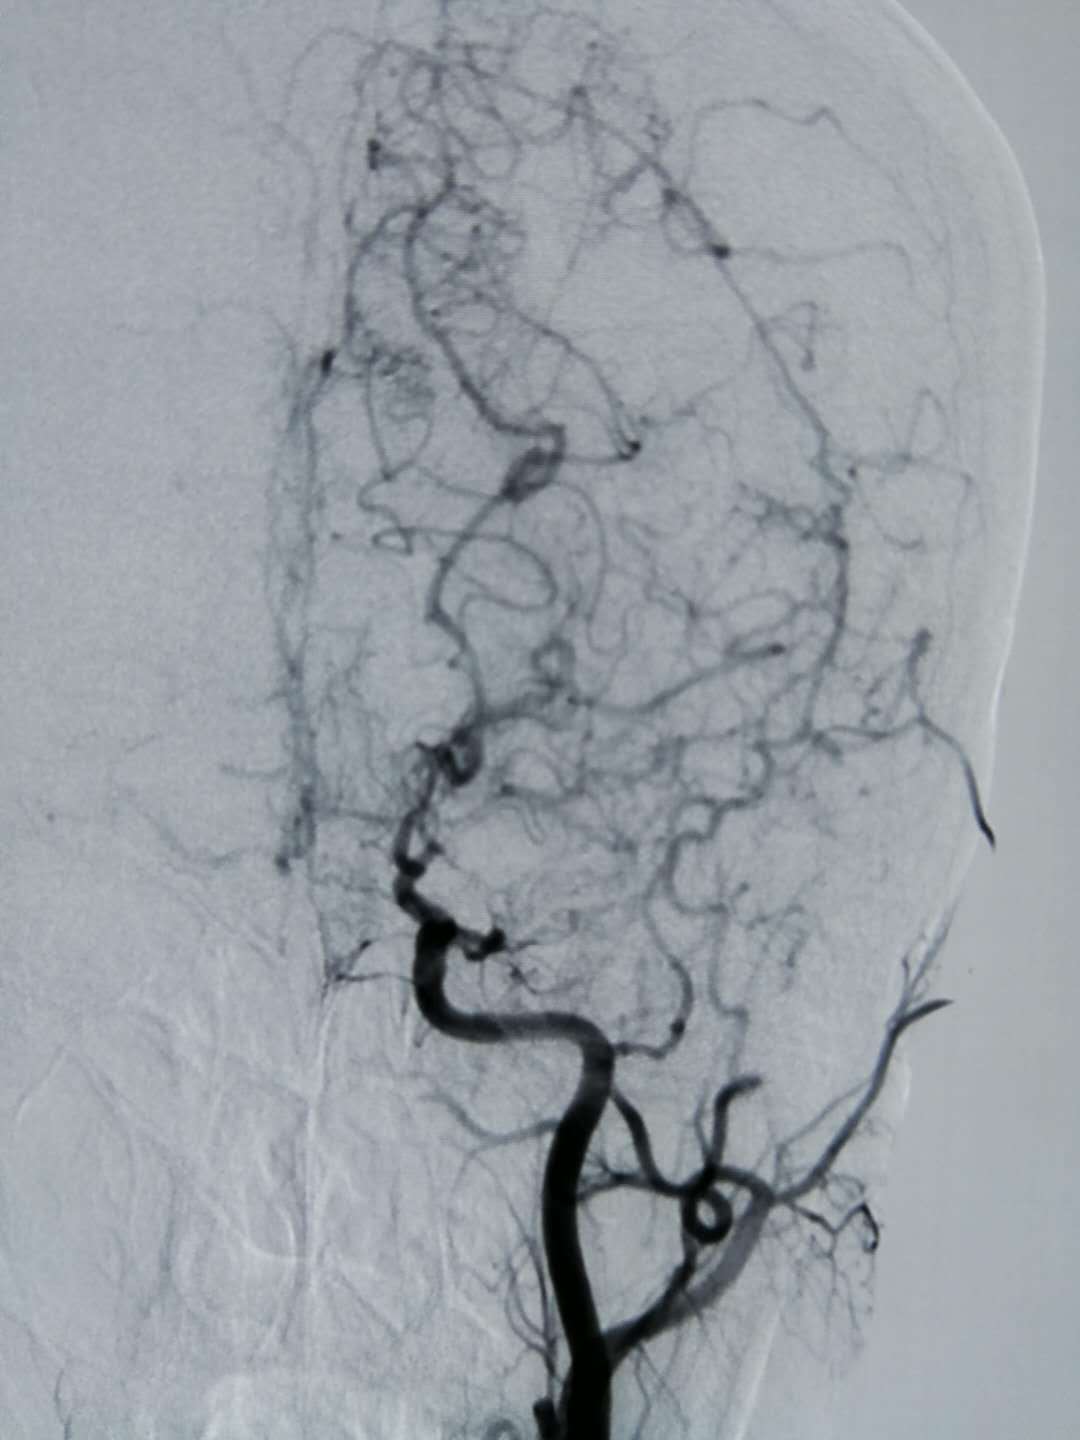

烟雾病是一种脑血管疾病,只是由于其在造影上显示像极了烟雾,所以才被命名为烟雾病。它的病因截止目前为止并不明确。但此病通常可见遗传因素。